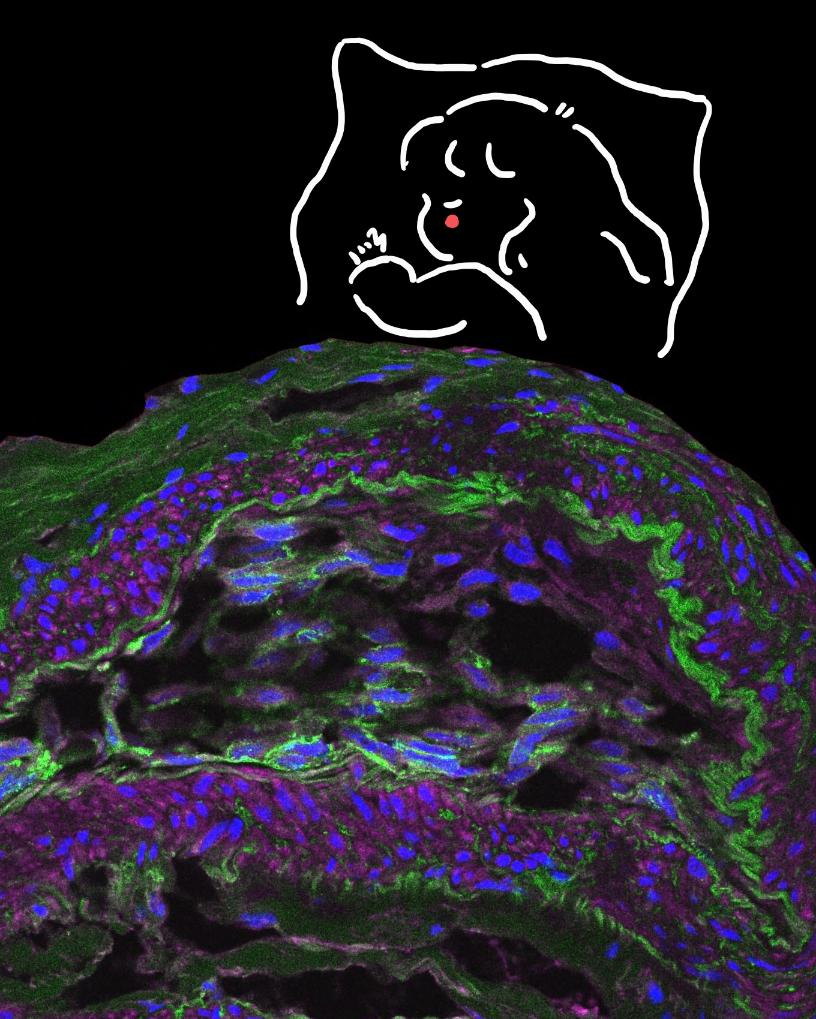

作品《深海寻梦》。新华网发(作者:沈静恬)

作品《深海寻梦》以人卵巢癌组织的免疫荧光染色图像为主画面,通过显微技术与艺术创作的融合,将生命科学的微观世界转化为一片深邃的“海洋”。画面上方手绘的“寻梦者”小女孩,以简笔线条勾勒出对科学之海的无限遐想。